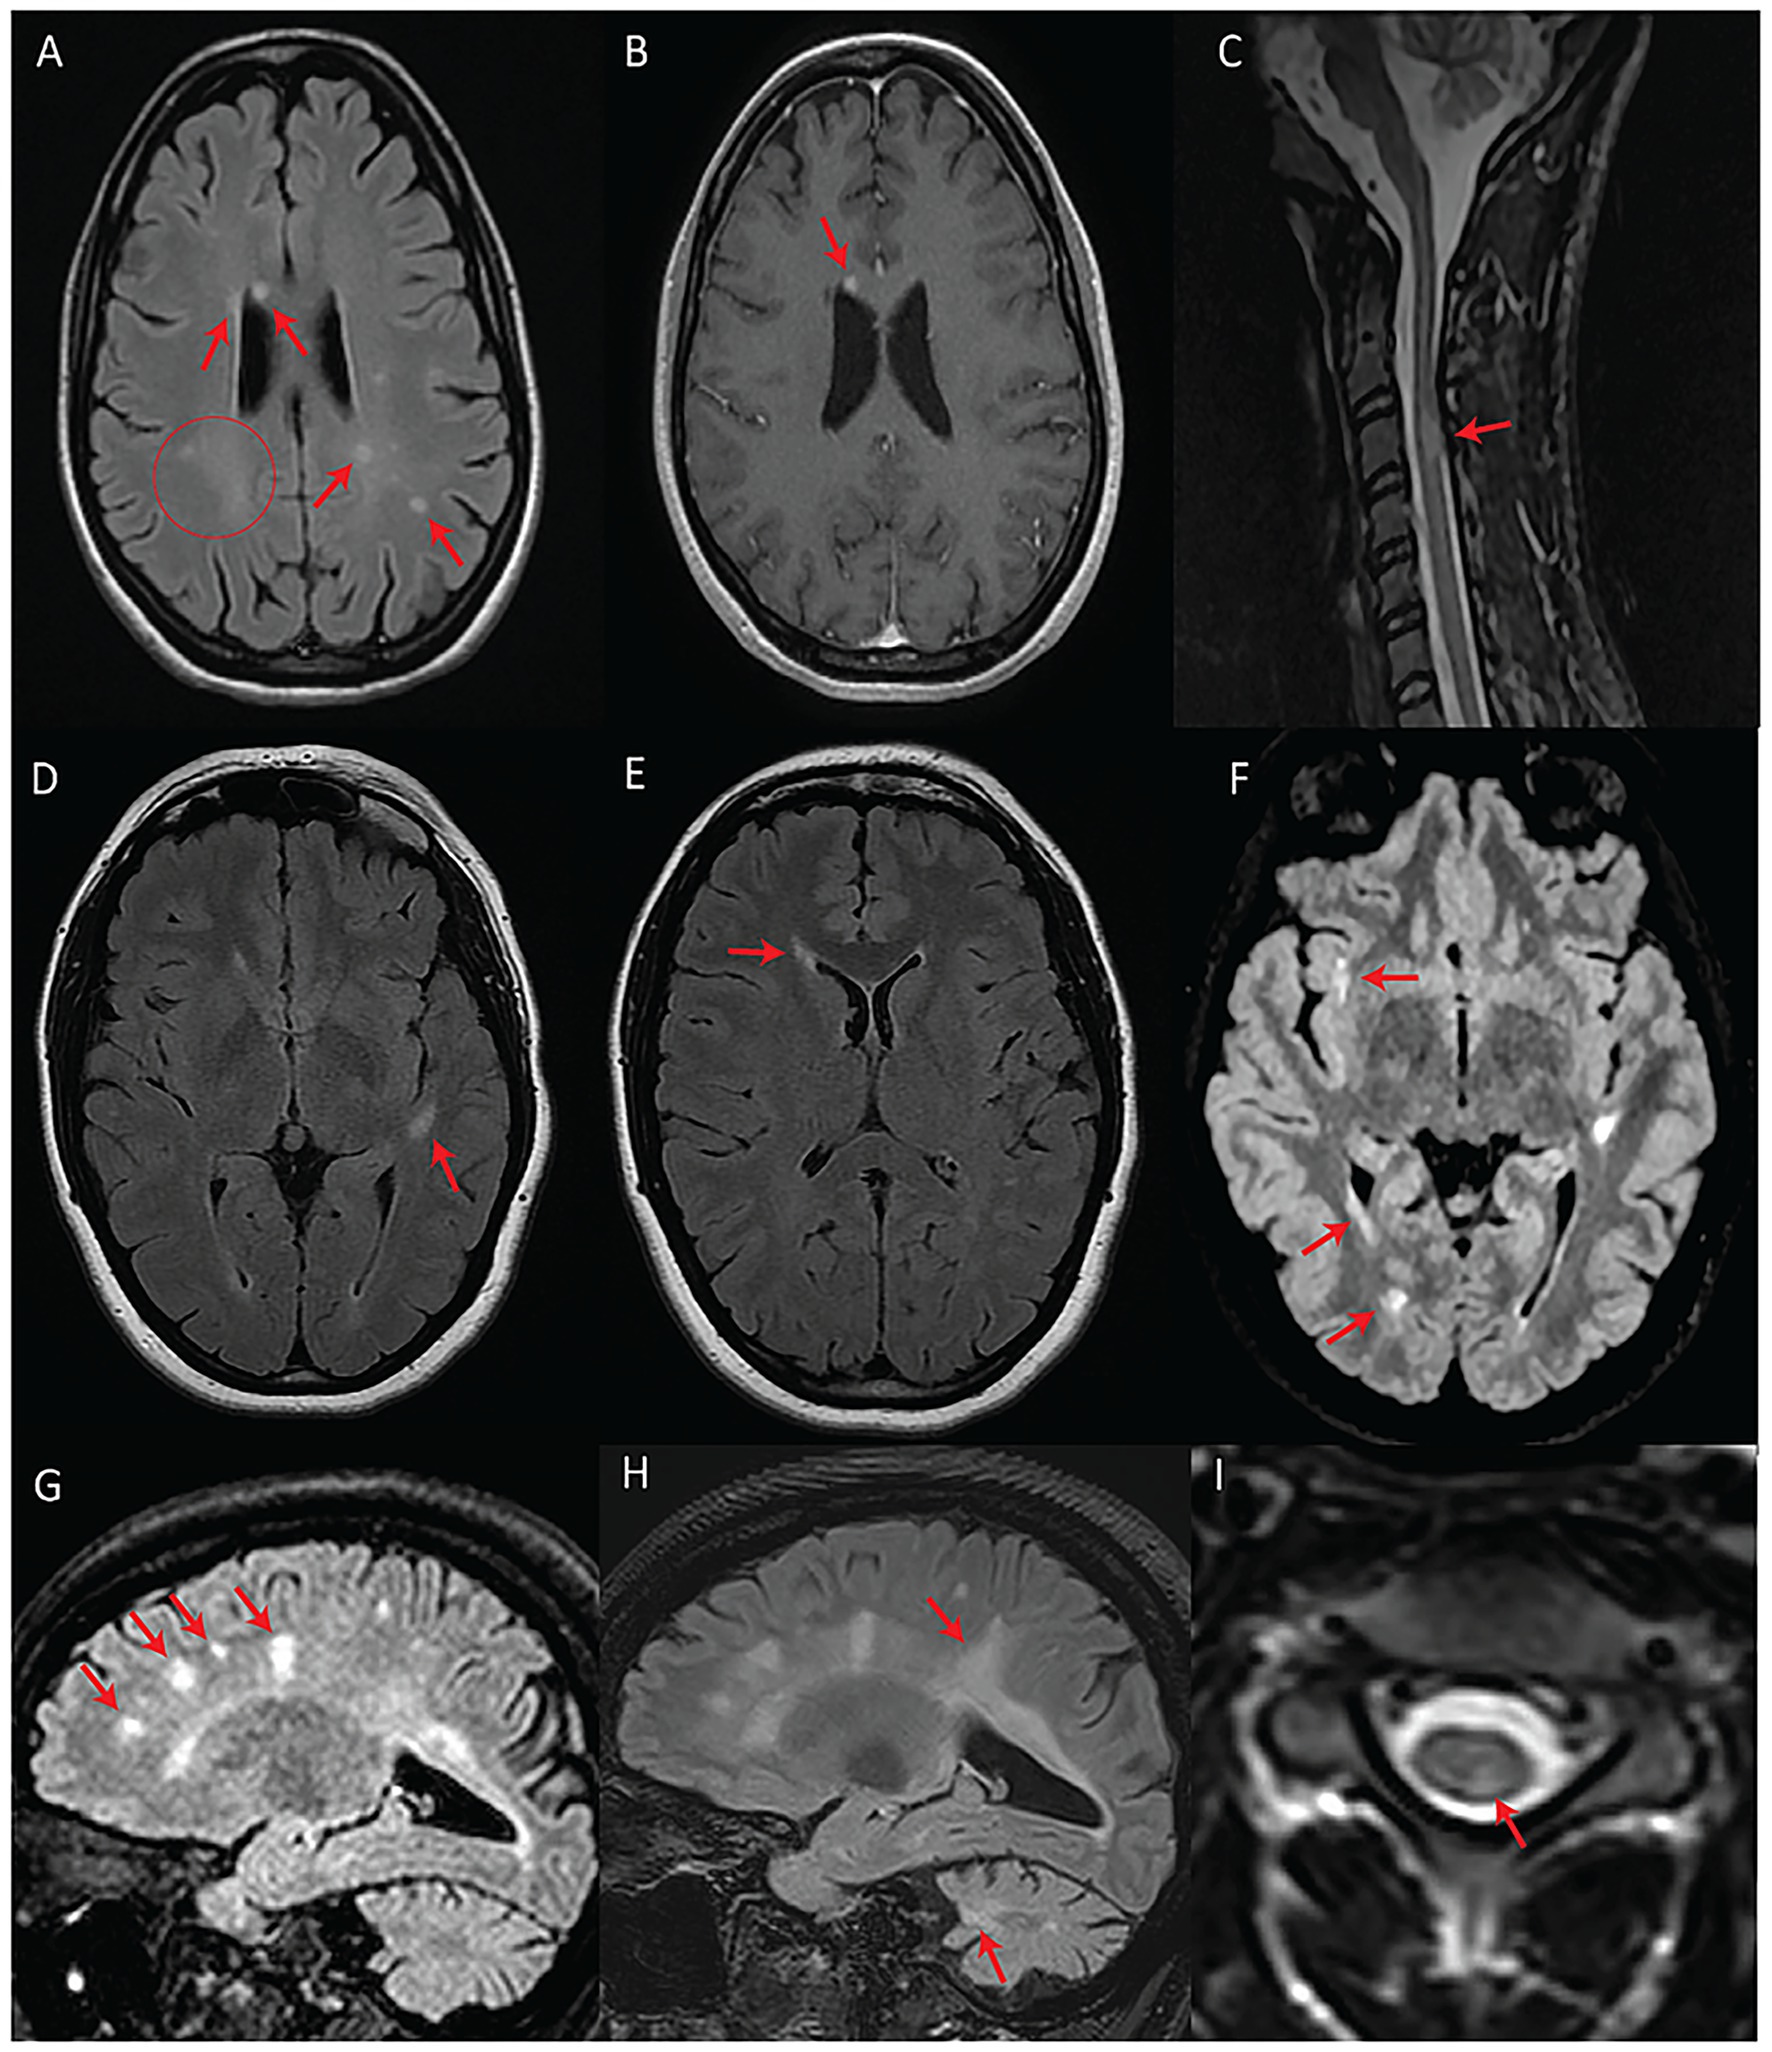

We detected T2-hyperintense white matter foci that were MS plaque-like (27–29) in seven subjects (n = 7/17; 41%) (Figures 2, 3). In four of these subjects (n = 4/17; 24%), the McDonald radiological criteria of dissemination in space and time were either fully (n = 3) or partially (n = 1) fulfilled, inciting consideration of a WFS-MS double diagnosis (Figure 2) (27). Some lesions in three of these four subjects showed gadolinium enhancement on T1-weighted imaging (Figure 2A), further supporting the existence of an underlying inflammatory process. Positive oligoclonal band status strongly supported a secondary diagnosis of MS (satisfaction of the full McDonald criteria, radiological and clinical) in the only two subjects for whom lumbar puncture was performed (#2 and #3). In both cases, a secondary diagnosis of MS was therefore communicated due to the presence of accompanying acute focal clinical deficits. MS treatment with teriflunomide was initiated in subject #3. Follow-up MRI after teriflunomide initiation documented stabilization of the multifocal white matter lesion load with worsening of pre-existing cerebellar atrophy and diffuse bilateral subcortical white matter involvement (Figures 2G–I). The observed locations and characteristics of MS-like focal lesions are summarized in Table 2.

Figure 2

Patients with fulfilled or partially fulfilled McDonald criteria. (A–C) Represent subject #2 (criteria fulfilled). (A) Axial T2-FLAIR image showing multifocal periventricular, callosal, and subcortical white matter lesions (arrows) with accompanying diffuse abnormal peritrigonal white matter signal (circle). (B) Post-gadolinium axial T1 image showing an enhancing callosal lesion. (C) Sagittal T2 image of the cervical and thoracic spinal cord showing a demyelinating lesion at the level of C3. (D–F) Represent subject #1 (criteria partially fulfilled). (D) Axial T2-FLAIR showing an oval-shaped lesion in the left temporal subcortical white matter. (E) Axial T2-FLAIR showing a periventricular lesion around the frontal horn of the right lateral ventricle. (F) Axial T2-FLAIR, performed 7 years after the first exam (D,E), showing new focal white matter lesions in the right insula, right periventricular white matter, and along the posterior horn of the right lateral ventricle. (G–I) Represent subject #3 (criteria fulfilled). (G) Sagittal T2-FLAIR showing multifocal white matter lesions perpendicular to the ventricular walls. (H) Sagittal T2-FLAIR, performed 4 years after initial MRI (G), demonstrating progression of the lesion burden in both the supra and infratentorial regions despite treatment with teriflunomide as of the first year in the 4-year interval. (I) Axial T2 spinal cord MRI showing a white matter lesion located in the left posterior cord at the C3 level.

In line with the hypothesis that some subjects in our study may be concomitantly suffering from WFS and MS, subject #3 responded to teriflunomide (Figures 2G–I). This was the only subject in our series who had started disease-modifying therapy for MS. While there is a possibility that the treatment had no impact on the natural course of WFS in this subject, it is plausible that underlying degenerative processes may have been exacerbated while inflammation was being suppressed. Even though the exact mechanisms contributing to this subject’s outcome remain undefined, simultaneous Wolframin/WFS1 deficiency and teriflunomide treatment might have imposed a significant mitochondrial stressor. Indeed, Wolframin/WFS1 plays an indirect, yet essential role in multiple facets of mitochondrial quality control putatively through modulation of Ca2+ homeostasis, while the mechanism of action of teriflunomide is the inhibition of dihydroorotate dehydrogenase, whose activity is intrinsically linked to the mitochondrial respiratory chain (19, 33). Thus, the classic WFS-associated neuroradiological features in this subject might have progressed, at least in part, because of a compounded mitochondrial insult, although dedicated studies are needed to validate this speculation.